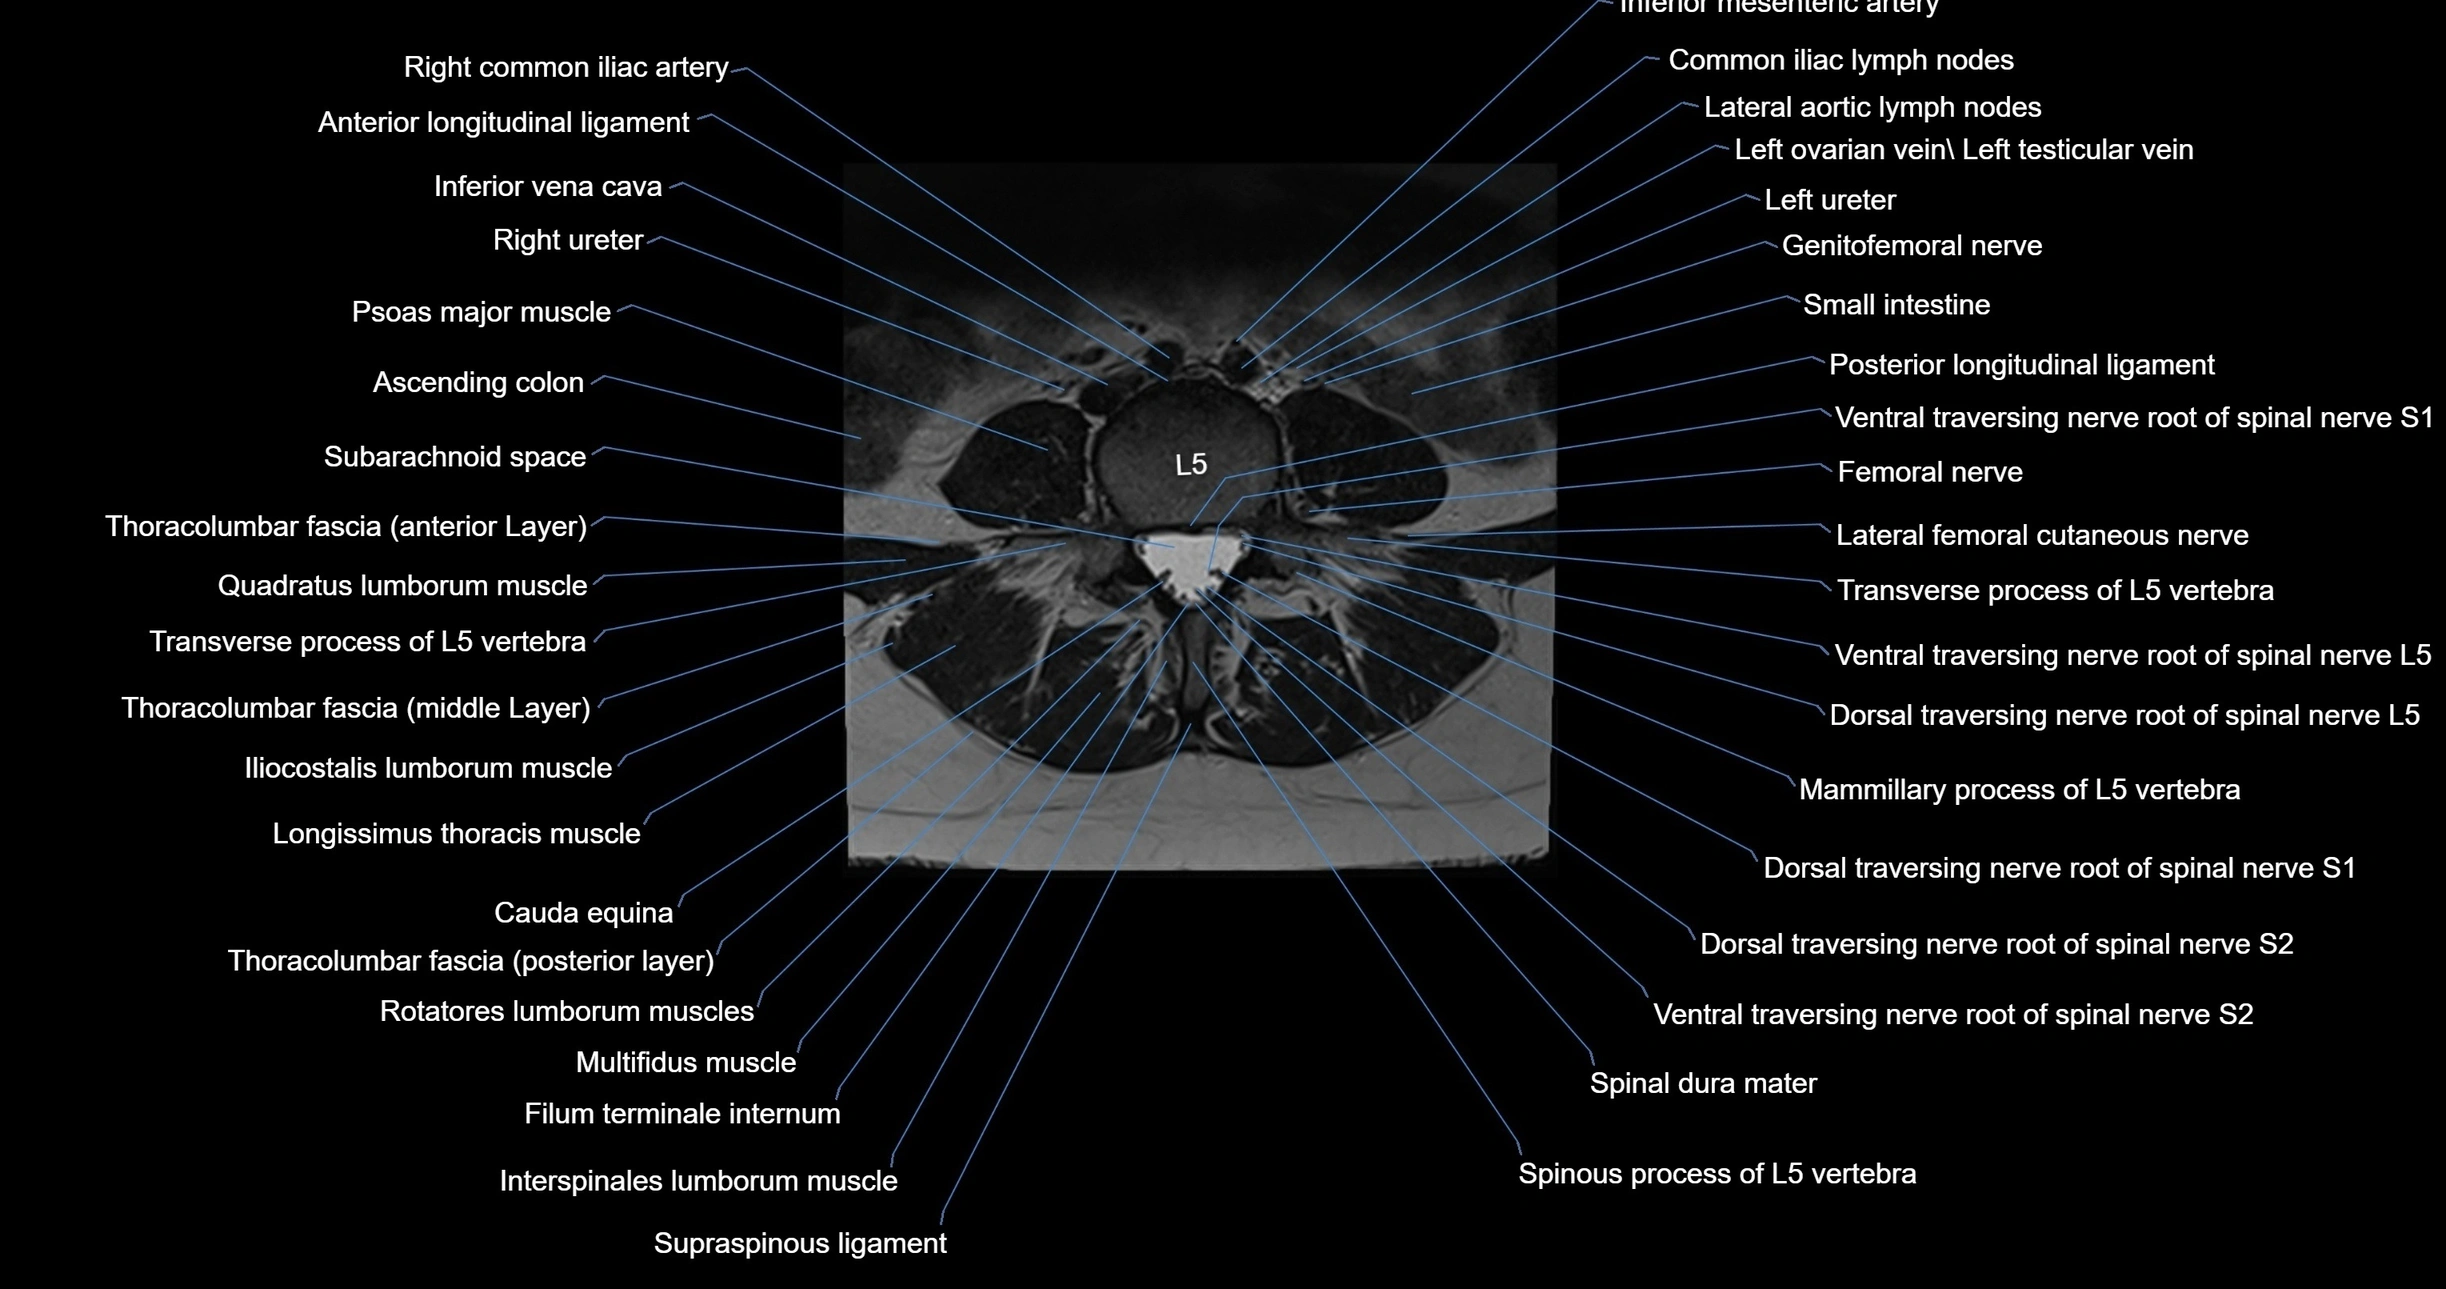

MRI images